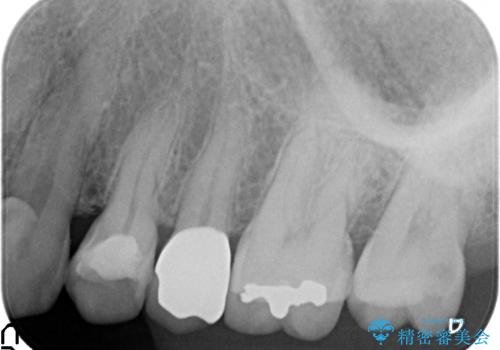

- 左上5番目の歯がしみるといらっしゃった方の症例です。

頬側の樹脂及び銀歯を除去後、オールセラミッククラウンにて補綴を行いました。

今回用いたオールセラミッククラウンはジルコニアフレームという白い素材の上にセラミックを盛っているため、審美性が非常に高いのが特徴です。

また、ジルコニアは人工ダイヤモンドの材料にも使われているほど高い強度を持っており、そのためオールセラミッククラウンは審美性だけでなく、奥歯やブリッジの補綴も可能とするクラウンです。